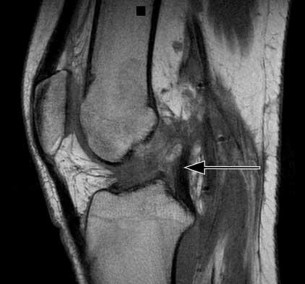

A 22-year-old man sustains an injury to his right knee in a motor vehicle collision. Figure 22a is the posterior stress radiograph of the involved knee, and Figure 22b is a selected MR image that identifies the injured structure.

CLINICAL SITUATION FOR QUESTIONS 22 THROUGH 25

Which relationship is noted for the structure identified by the arrow in Figure 22b? 24

The stress radiographs demonstrate posterior instability of the right knee in flexion. The MR images demonstrate injury to both the anterior and posterior cruciate ligament (PCL), with the stump identified with the arrow on the MR image (Figure 22b). The PCL has 2 functional bands. The anterolateral bundle originates from the roof of the intercondylar notch. It runs in a posterolateral direction onto the tibial crest between the posterior attachment of the medial and lateral menisci. During a double-bundled posterior ligament reconstruction, the

anterolateral bundle is tensioned with the knee in a position of mid flexion. The posteromedial bundle has a variable pattern of tension both in extension and in high flexion. Tensioning of the posteromedial bundle in extension may contribute to resistance against knee hyperextension.

The meniscofemoral ligaments are variably present. Although 93% of knees have been reported to have at least 1 meniscofemoral ligament present, both ligaments are simultaneously present in approximately 50% of knees. The ligament of Humphrey (anterior meniscofemoral ligament) and ligament of Wrisberg (posterior meniscofemoral ligament) are delineated by their anatomic relationship to the posterior cruciate.